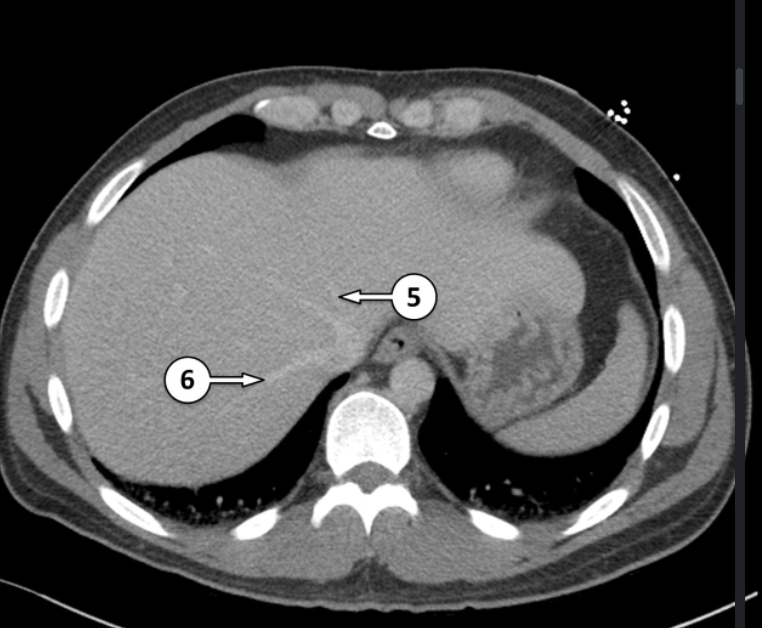

Please label 5 and 6

left hepatic vein

right hepatic vein